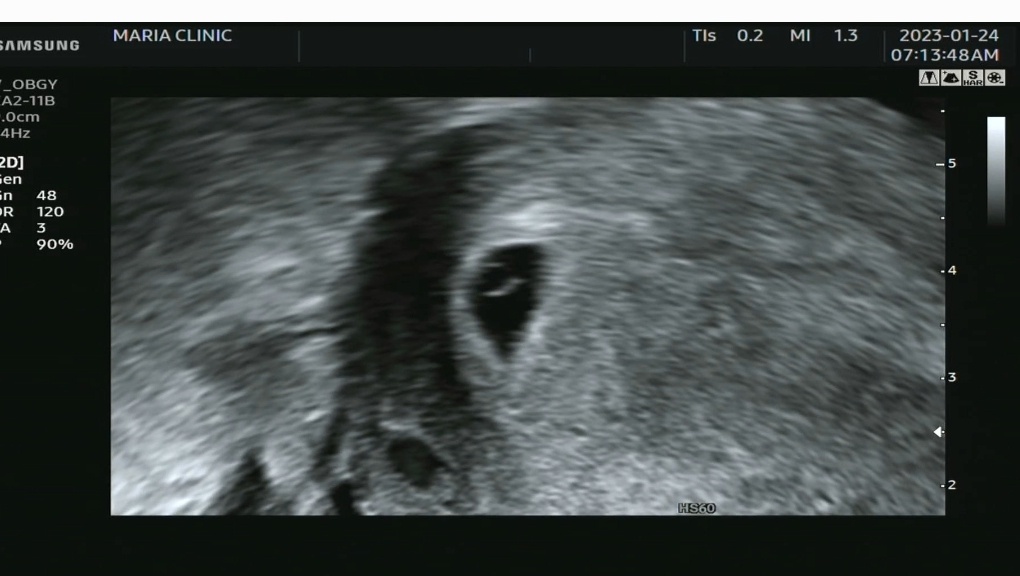

아직 세상에 나오진 않았지만 초음파를 통해 아기집을 보았고 인공수정 1차 시험관 1차에 나는 아빠가 되었다. 아빠가 되기 위한 일부 과정을 겪어보니 많은 생각이 들었다. 생각을 하면서 난임 시술 과정을 복기해 보니 남편이 해줘야 하는 역할이 크다는 생각이 들었다. 내가 경험한 과정과 당시의 감정들을 적고 미처 몰랐던 상황들을 공유하고자 한다. 좋은 남편과 좋은 아빠가 되는 것에 관심이 있거나, 임신이 안 되는 것에 대해 가볍게 생각하는 남편에게 도움이 되면 좋겠다는 생각으로 이 글을 작성해 나아가고 있다.

이런 과정 끝에 피검사를 통해 임신을 확인하였고 아빠가 되었다. 이 글은 아이가 5주 차 일 때 작성했는데 공 들여서 내용을 쓰다 보니 벌써 7주 차가 되었다. 이제는 아이의 심장도 생겼다. 여기에 적은 글들 외에도 남겨두고 싶은 내용이 많은데 그렇게 했다간 글 완성을 못 시킬 거 같아 이 정도로만 작성하고자 한다. 난임 시술에 대한 실질적인 비용은 포카리, 병원비, 시술 후 음식 값을 하면 200~240만 원 정도 잡아야 될 거 같다.